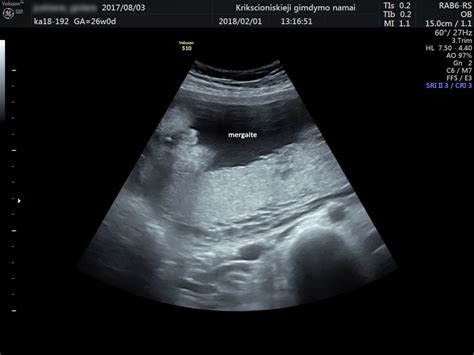

Ultragarsinis tyrimas, dažniau vadinamas tiesiog echoskopija, yra neinvazinis ir vienas pagrindinių tyrimų nėštumo metu, leidžiantis įvertinti vaisiaus raidą, augimą ir būklę, ar nėra jokių nukrypimų nuo įprastos nėštumo eigos. Taip pat jo dėka galima pastebėti negimdinį nėštumą, kai apvaisinta kiaušialąstė vystosi ne gimdos ertmėje, o už jos ribų - tai gali būti pavojinga ne tik moters sveikatai, bet ir gyvybei.

Pagal LR sveikatos apsaugos ministerijos informaciją, šis tyrimas reikalingas bent du kartus per nėštumą. Pirmojo nėštumo laikotarpio ultragarsinė patikra turėtų būti atlikta 11-13 savaičių, o antrojo nėštumo laikotarpio ultragarsinė patikra įprastai atliekama šiek tiek vėliau, apie 18-20 nėštumo savaičių, kai vaisius būna paaugęs, jau yra susiformavusi jo anatomija ir tyrimo metu gydytojas gali pamatyti bei įvertinti, ar vaisiui viskas gerai, ar nėra jokių matomų pakitimų.

Geriausia, kai ultragarsinis tyrimas yra atliekamas iškart - 5-7 nėštumo savaitę. Tai leidžia įsitikinti, jog gemalinė pūslytė yra gimdoje ir joje užsimezgęs embrionas, galime matyti pulsuojančią širdelę, nes pasitaiko atvejų, kai pūslytė, deja, būna tuščia.

Tyrimo metu įvertinama, ar vaisius vienas, ar nėštumas daugiavaisis. Ultragarsinis tyrimas dažniausiai atliekamas transabdominaliniu būdu, per nėščiosios pilvo sieną.

Tiriant ultragarsu ankstyvoje nėštumo stadijoje atliekamas sprando raukšlės matavimas dėl galimų chromosominių vaisiaus ligų, vėliau matomos smegenų struktūros, stuburo ir kitų vidaus organų vystymasis, nustatomas tikslus vaisiaus dydis, gimdymo data, lytis. 34-35 nėštumo savaitę tiriama fetoplacentinė (tarp vaisiaus ir placentos) virkštelės kraujotaka.